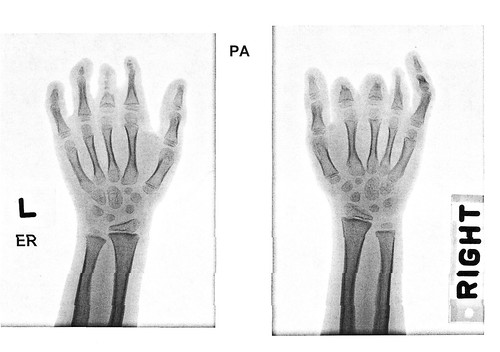

On July 17, 2015 Amelie had surgery on some of her toes. The banding that affects her fingers was also causing problems with her toes so Texas Scottish Rite said that they could give her some relief.